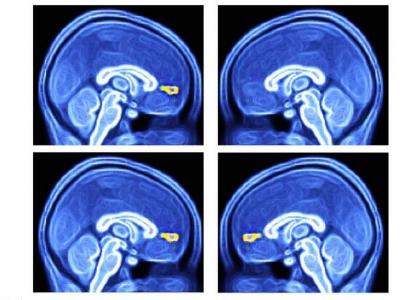

Des scientifiques du Wake Forest Baptist Medical Center (Caroline du Nord) ont mis au point une approche diagnostique simple des troubles du spectre autistique TSA) : l'équipe mesure la réponse d'enfants autistes à différents signaux environnementaux sous imagerie par résonance magnétique fonctionnelle (IRMf). Chez les enfants autistes (visuels du haut) la présentation unique d'objets ou de visages favoris n'active pas une zone spécifique du cerveau, le cortex préfrontal médial ventral. Ce test d’imagerie simple est décrit dans la revue Biological Psychology.

L’équipe a testé la réactivité du cortex préfrontal médial ventral du cerveau (vmPFC : ventral medial prefrontal cortex) aux signaux visuels représentant une interaction sociale « de grande valeur », chez 40 jeunes participants âgés de 6 à 18 ans, dont 12 diagnostiqués avec TSA et 28 suivant un développement normal. Les participants ont passé l’IRMf tout en visualisant 8 images de personnes ou d'objets, chacune plusieurs fois. Chaque série d'images comprenait 2 images choisies de manière individuelle représentant la personne et l’objet préférés de chaque participant. L’expérience montre que la réponse moyenne du vmPFC est significativement plus faible dans le groupe de participants atteints de TSA.

- Le simple recours à des images du patient et à l’IRMf pour capturer 30 secondes de données s’avère donc suffisant pour diagnostiquer l’autisme. « La façon dont le cerveau réagit à ces images est cohérente avec l’hypothèse selon laquelle les cerveaux des enfants autistes ne codent pas la valeur de l'échange social de la même manière que les enfants en développement typique », expliquent les chercheurs.